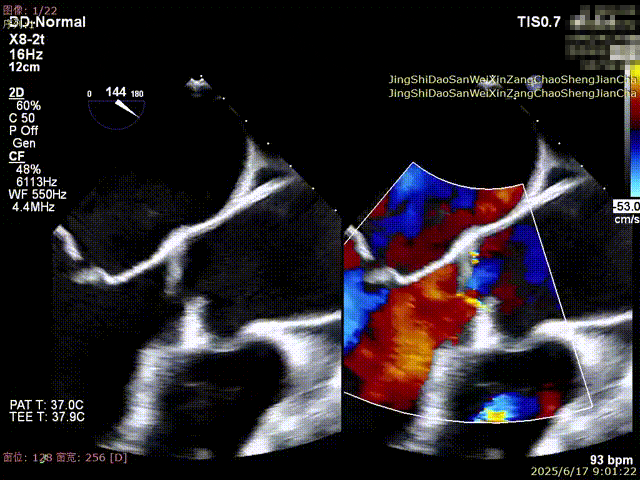

DMR:二尖瓣重度反流5+,P2区脱垂连枷,AP:38mm,MVA:6cm²,反流宽度14.2mm,反流2区,P2区脱垂范围14mm,连枷间距4mm,脱垂高度6.6mm,瓣环直径37mm。

术前超声

全麻后,首先在心前区的肋间切开3-4CM小切口,暴露心脏的心尖位置,心尖穿刺后进入导丝,利用导丝交换导管鞘完成通路建立。将系统送入左心房,顺利到达二尖瓣病变区域。在经食道超声引导下,术者通过反复评估二尖瓣反流位置、抓捕位置、反流程度,在2区主动脉瓣与二尖瓣闭合线垂直进行巧妙夹合,最终植入一枚ValveClamp®MVC-Ⅲf夹。超声评估夹子固定良好,组织桥完整,无葫芦征,位置、轴向均符合预期。患者术后反流程度从大量转至少量,手术取得圆满成功。患者恢复良好,已经顺利出院。